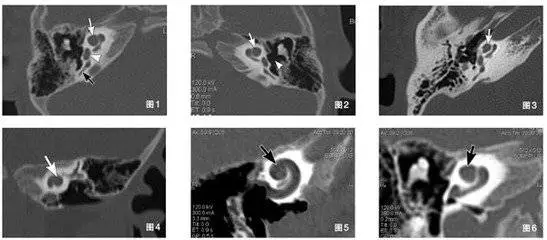

圖1-6顯示患者雙側(cè)耳蝸mondini畸形

多排螺旋CT主要觀察內(nèi)耳結(jié)構(gòu)(骨迷路結(jié)構(gòu))。耳蝸畸形中,除Michel畸形、耳蝸未發(fā)育為手術(shù)的絕對(duì)禁忌癥,其他類(lèi)型內(nèi)耳畸形均非人工耳蝸植入的禁忌癥。不同內(nèi)耳畸形術(shù)后可能出現(xiàn)不同的并發(fā)癥,多層螺旋CT及其后處理技術(shù),能從不同角度、由二維到三維立體顯示內(nèi)耳結(jié)構(gòu)的大體形態(tài),對(duì)不同畸形做出細(xì)致的分類(lèi),能幫助臨床醫(yī)生更好地預(yù)測(cè)手術(shù)中可能遇到的問(wèn)題,合理地選手術(shù)方式和判斷預(yù)后,有很高的應(yīng)用價(jià)值。